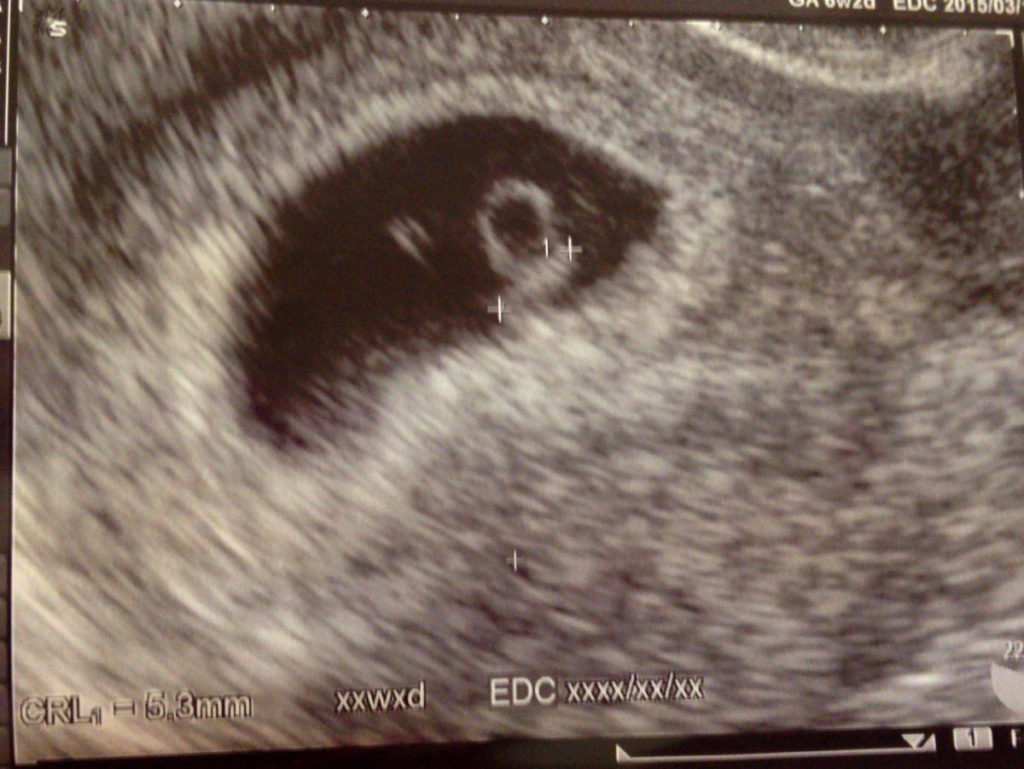

経口中絶薬は妊娠初期、妊娠9週0日までの妊婦さんが対象になり、妊娠の継続に必要な働きをする黄体ホルモンの働きを抑える「ミフェプリストン」を内服し、2剤目となる子宮を収縮させる「ミソプロストール」を36~48時間後に内服します。治験では、2剤目の内服後24時間までに93.3%が中絶に至ったようです。